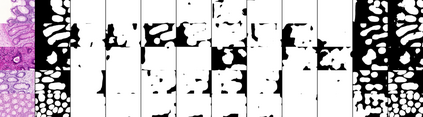

Weakly-supervised learning (WSL) has recently triggered substantial interest as it mitigates the lack of pixel-wise annotations. Given global image labels, WSL methods yield pixel-level predictions (segmentations), which enable to interpret class predictions. Despite their recent success, mostly with natural images, such methods can face important challenges when the foreground and background regions have similar visual cues, yielding high false-positive rates in segmentations, as is the case in challenging histology images. WSL training is commonly driven by standard classification losses, which implicitly maximize model confidence, and locate the discriminative regions linked to classification decisions. Therefore, they lack mechanisms for modeling explicitly non-discriminative regions and reducing false-positive rates. We propose novel regularization terms, which enable the model to seek both non-discriminative and discriminative regions, while discouraging unbalanced segmentations. We introduce high uncertainty as a criterion to localize non-discriminative regions that do not affect classifier decision, and describe it with original Kullback-Leibler (KL) divergence losses evaluating the deviation of posterior predictions from the uniform distribution. Our KL terms encourage high uncertainty of the model when the latter inputs the latent non-discriminative regions. Our loss integrates: (i) a cross-entropy seeking a foreground, where model confidence about class prediction is high; (ii) a KL regularizer seeking a background, where model uncertainty is high; and (iii) log-barrier terms discouraging unbalanced segmentations. Comprehensive experiments and ablation studies over the public GlaS colon cancer data and a Camelyon16 patch-based benchmark for breast cancer show substantial improvements over state-of-the-art WSL methods, and confirm the effect of our new regularizers.